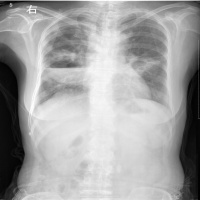

X线检查X线检查在肺结核的诊断上有很高的价值,大致表现有:斑点结节状,密度较高边缘清楚的纤维包围的干酪灶;云雾状或片状,密度较淡,边缘完整密度不均匀的球形病灶;具有环形边界透亮葋的空洞形成。

X线检查一般患者X线平片上极少有征象。重度患者胸片显示一侧或双侧下肺纹理增粗,絮乱以及呈蜂窝壮阴影或见有小的液平面。支气管造影确定扩张的部位,范围形状并可决定治疗方案。

X线检查病变初期为片状浓密阴影,后渐向周围肺组织扩展,而且不受叶间胸膜限制脓腔形成后则内壁光滑,常有液平,脓腔周围有炎症浸润后期脓腔渐缩小,炎润渐消退,最后形成少许条索状阴影而痊愈 一般根据急性发病史临床表现、X线检查,痰细菌学检查和诊断断性治疗诊断不困难。

X线检查恶性肿瘤转移常为多发性,单发性者少见。多发性乾为圆形卵圆形、粟粒状,大小相仿边缘不整,发展较快。一般原发灶不易诊断须仔细设法寻找。

X线检查肺栓塞可引起肺动脉高压征象,多发性小的肺栓塞呈支气管肺炎样弥散的浸润阴影,较大的栓塞则发生肺梗死呈楔形阴影。肺血管造影可显示直径0.5mm以上的血管能直接看到栓塞的部位和范围。也为手术治疗作好准备。

X线胸片呈现双侧肺野斑片状模糊阴影以中、下野为著。病原学和血清学检查可以确定诊断。